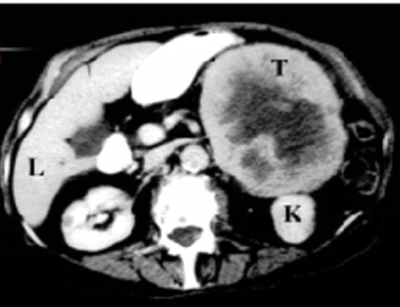

- הסריקה הטומוגרפית מאפשרת הדגמה מהימנה ומדויקת של בלוטות יותרת-הכליה והפתולוגיות שלהן. זו בדיקת הבחירה לבירור גוש בבלוטת יותרת-הכליה (תצלום 5.14).

השאת רוכבת על הקוטב העליון של הכליה. מרכזה נמקי. T - הגוש בבלוטת יותרת-הכליה; L - כבד; K - כליה